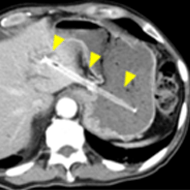

超音波内視鏡下胆道ドレナージ術(EUS-BD)

ERCPによる経乳頭的な胆道ドレナージが困難な場合に胃あるいは十二指腸から胆管を穿刺し、 ステントを留置します。従来のPTBD(経皮経肝的胆道ドレナージ)と比較して、チューブが 体外に出ることがなく、金属ステントを用いることで長期間のステント開存が期待できます。

閉塞性黄疸に対するEUS-BD十二指腸球部から総胆管に直接金属ステントを留置しています